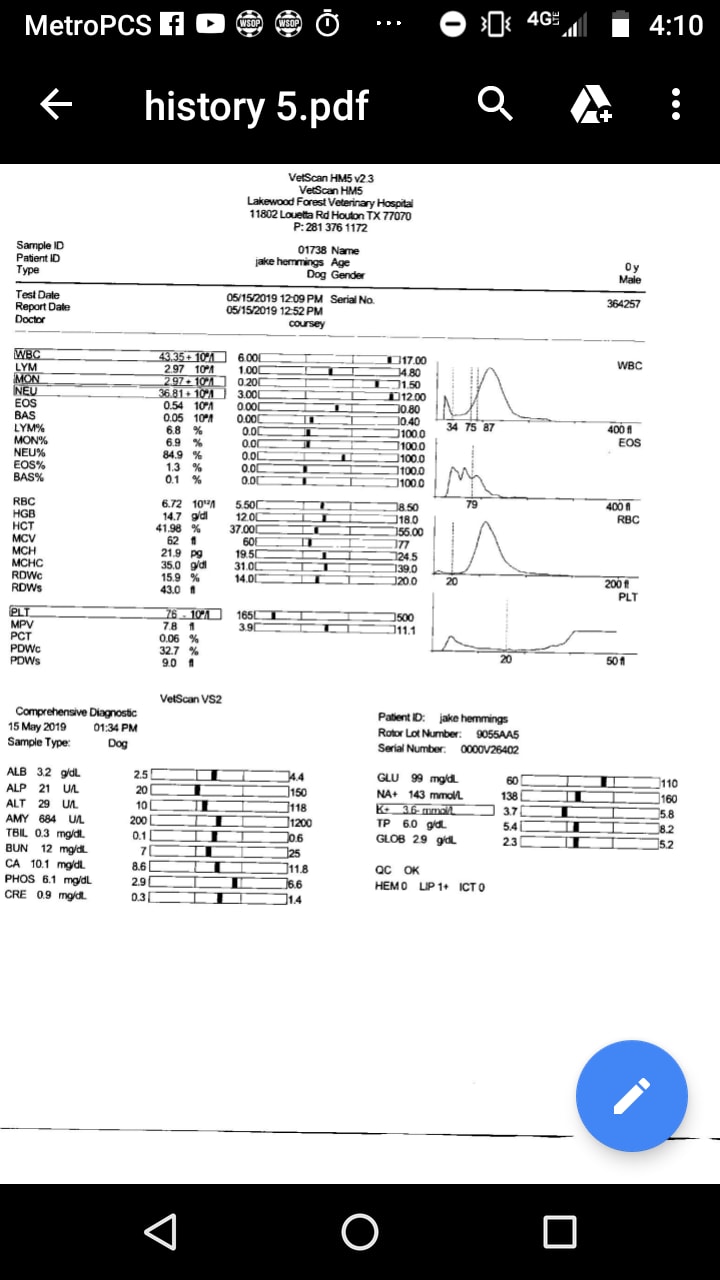

Senior dog has enlarged testicles, swollen legs, and high WBC. Is it cancer?

Pet's info: Dog | German Shepherd | Male | 10 years and 7 months old | 98 lbs

I keep getting conflicting answers. Vet said he has colorectal or prostate cancer. Two here say gas and feces build up. His testicles are like orange size and Dr said swell in back legs is called edema compromised circulation. Vets here don't have the patient and can go only by the attached x-rays. He also has impacted fistulas. Dr recommend euthenasia. Gas build up isn't the same as cancer Blood work shows wbc 43.35 see attached

It sounds like prostatitis and/or cancer. I'm not exactly sure what your question is. We don't have enough information to be able to guide you to a decision. I do not think it is simple gas/constipation. The fistulas and the size of the testicles is very concerning. I think you should consider taking him to an internal medicine specialist for a consult. ( https://www.gcvs.com/service/internal-medicine/ ) ( https://urbananimalveterinary.com/services/internal-medicine/ )